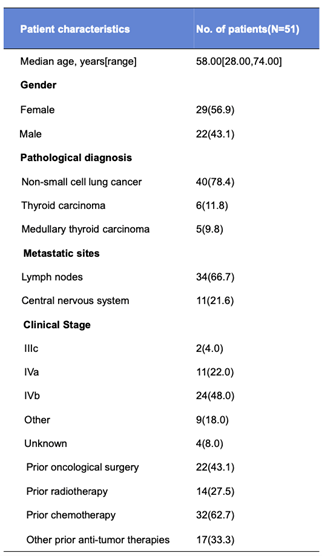

жүҖжңүеҸ—иҜ•иҖ…еқҮжіӣиө·жІ»з–—зӣёе…ідёҚиүҜдәӢеҠЎпјҲTRAEпјү�пјҢпјҢпјҢпјҢ�пјҢ�пјҢжңҖеёёи§Ғзҡ„TRAEдёәASTеҚҮй«ҳпјҲ64.7%пјүгҖҒALTеҚҮй«ҳпјҲ58.8%пјүгҖҒTBILеҚҮй«ҳпјҲ45.1%пјүгҖҒWBCйҷҚдҪҺпјҲ43.1%пјүгҖҒNEUTйҷҚдҪҺпјҲ33.3%пјүгҖҒй«ҳе°ҝй…ёиЎҖз—ҮпјҲ31.4%пјүгҖҒй«ҳиЎҖеҺӢпјҲ29.4%пјүгҖҒдҪҺзҷҪеҚөзҷҪиЎҖз—ҮпјҲ25.5%пјүгҖҒSCrеҚҮй«ҳпјҲ23.5%пјүе’ҢеӨҙз—ӣпјҲ23.5%пјү[1]�гҖӮгҖӮгҖӮгҖӮ�гҖӮ

BYS10зҡ„иў’йңІйҮҸд»ҘеүӮйҮҸдҫқиө–жҖ§зҡ„ж–№жі•д»Һ25mgеўһж·»еҲ°600mg�гҖӮгҖӮгҖӮгҖӮ�гҖӮе…¶дёӯ�пјҢпјҢпјҢпјҢ�пјҢ�пјҢ100 ~ 300 mg BIDз»„жҠҘе‘Ҡзҡ„3 ~ 4зә§TRAEпјҲпјһ5%пјүеҢ…жӢ¬ASTеҚҮй«ҳпјҲ25.5%пјүгҖҒALTеҚҮй«ҳпјҲ13.7%пјүе’Ңй«ҳиЎҖеҺӢпјҲ9.8%пјү�гҖӮгҖӮгҖӮгҖӮ�гҖӮдёҘйҮҚдёҚиүҜдәӢеҠЎ7дҫӢ[1]�гҖӮгҖӮгҖӮгҖӮ�гҖӮ

еӣҫ2.жё…йқҷжҖ§ж•Ҳжһң